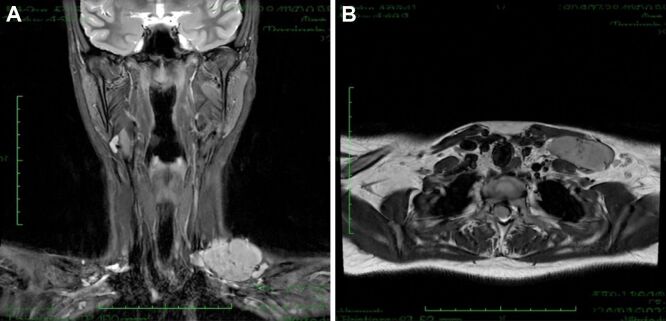

卡斯特曼病(CD)是一组淋巴细胞增生性疾病,以淋巴结异常肿大和多种症状为特征。只有少数病例发生在头颈部。根据临床表现和演变,该病可分为两大亚型:单中心 CD(UCD)和多中心 CD(MCD),前者以单个淋巴结或单个淋巴结链肿大为特征,后者以多个淋巴结和淋巴结区域受累为特征,伴有更重要的全身症状,预后较差。CD 也被称为 "伟大的模仿者",很容易被误诊,因为它与其他病变具有相似的临床和影像学特征,主要是在颈部发现时。在这些病例中,组织病理学(HP)和免疫组织化学(IHC)的相关性对于准确诊断和制定适当的治疗方案至关重要。有鉴于此,我们报告了一例罕见病例,患者是一名 15 岁的年轻女性,其锁骨上肿块缓慢扩大且孤立存在。我们对该病例进行了切除活检,结果证实其为透明-血管型 CD。截至本文撰写之时,没有证据表明该病复发或出现新的肿大 LN。我们还回顾了 CD 的临床和 HP 特征,以及它给诊断和治疗带来的挑战。

Castleman disease (CD) is a group of lymphoproliferative disorders characterized by abnormal enlargement of lymph nodes (LNs) and a wide range of symptoms. Only a few cases are found in the head and neck. Based on clinical presentation and evolution, the disease can be classified into two main subtypes: unicentric CD (UCD), characterized by the enlargement of a single LN or a single LN chain, and multicentric CD (MCD), characterized by the involvement of multiple LNs and regions, with more important systemic symptoms and a poor prognosis. CD is also known as "the great mimicker" and can be easily misdiagnosed, sharing similar clinical and imaging characteristics with other pathologies, mainly when it is found in the neck. A histopathological (HP) and immunohistochemical (IHC) correlation is essential in these cases to accurately diagnose and establish the proper treatment plan. In light of this, we present a rare case of a 15-year-old young female with a slowly expanding, isolated supraclavicular mass. An excisional biopsy was performed, and the results confirmed the presence of CD, hyaline-vascular type. As of this writing, there was no evidence of recurrence or new enlarged LNs. We also review CD's clinical and HP features and the diagnostic and treatment challenges it poses.